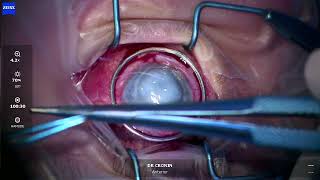

Dr Cronin provides these videos as an educational resource for training ophthalmologists, other ophthalmologists and patients. Dr Cronin specialises in corneal and anterior segment diseases including LASIK, laser eye surgery, cataracts, keratoconus, Fuchs endothelial dystrophy and pterygium surgery.